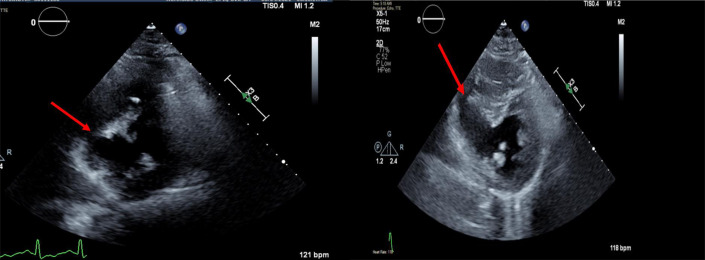

Echocardiography is diagnostic, evaluating size and location of a left-to-right shunt (Fig. 1 ), biventricular function, presence of LV thrombus, mitral regurgitation, pulmonary artery and right-sided pressures, free-wall rupture and tamponade.4 Right heart catheterization shows a diagnostic step-up in oxygenation between the right atrium and pulmonary artery and elevated pulmonary-to-systemic flow ratio (up to 8:1) depending on the ventricular septal defect (VSD) size.4 Left heart catheterization commonly shows a complete coronary obstruction without collateral circulation and left ventriculography shows contrast in the right ventricle and pulmonary artery.4 Anterior and apical ischemic VSDs are caused by infarcts in the left anterior descending (LAD) territory and posterior VSDs are due to inferior infarcts.4 Right ventricular infarction or ischemia with severe dysfunction is an important feature of VSDs caused by acute, proximal right coronary occlusion.4 Posterior VSDs are often accompanied by mitral valve regurgitation commonly secondary to ischemic remodeling.4

Fig. 1.

Ventricular septal defect with left-to-right shunting (red arrow).